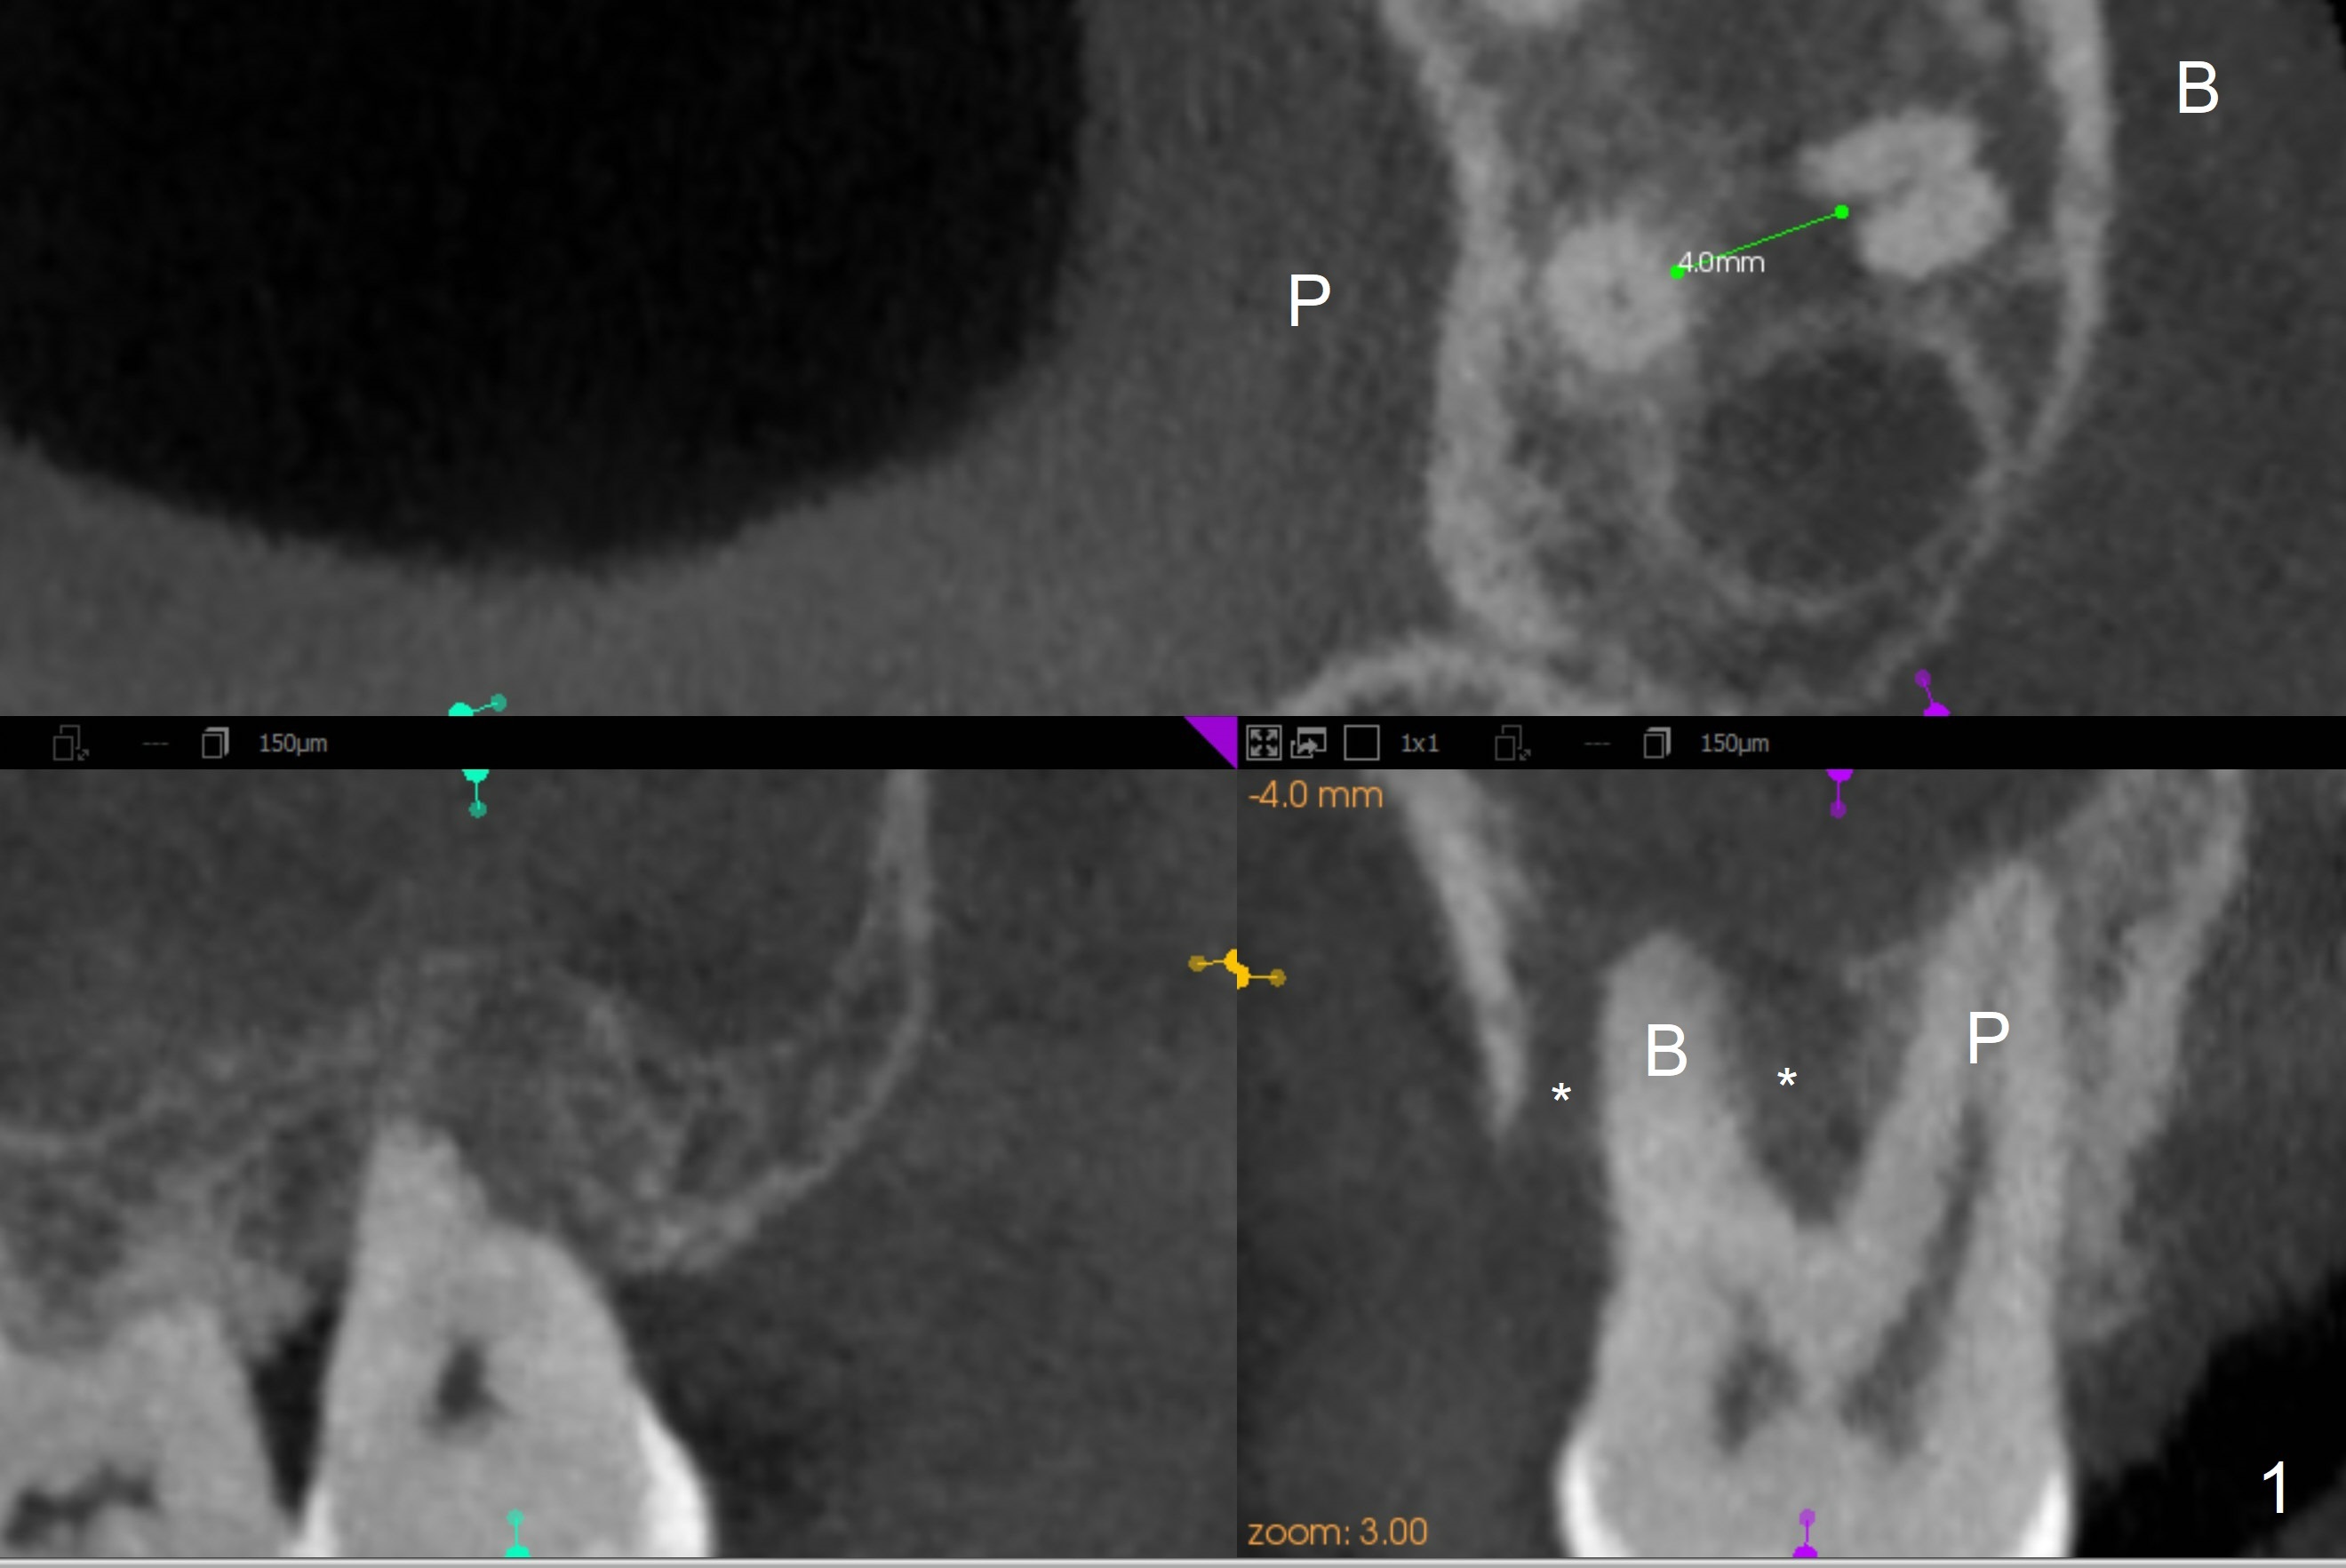

A 40-year-old man develops an abscess around the buccal roots of the tooth #15 several years after extraction of the symptomatic tooth #16. The pattern of infection is similar to that between #17 and 18. There is severe bone loss (Fig.1 *) around the fused buccal roots (Fig.2). It appears that an immediate implant (green) placed in the septum (Fig.4) has better position and angulation for restoration than the one placed in the palatal socket (Fig.3). Pink: cuff of abutment (blue); yellow: Osteogen Plug; red: bone graft.